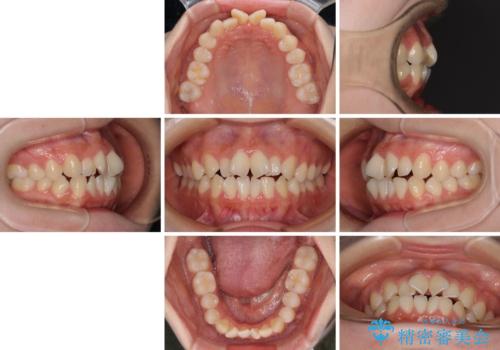

- 前歯のデコボコと非接触の上下前歯を気にして来院された患者様です。

上下前歯の隙間は舌の突出癖によるもので、隙間改善のためには舌のトレーニングがとても重要となります。

口元の突出感はないため、抜歯矯正の適用ではありませんが、デコボコを解消する際に外側に拡大されてしまうと治療前と比べて出っ歯になった印象にもなるため、舌の突出癖の改善が必須となります。

インビザラインによる治療は自己管理が煩わしいとのことで、ワイヤー装置による矯正治療を行うこととしました。